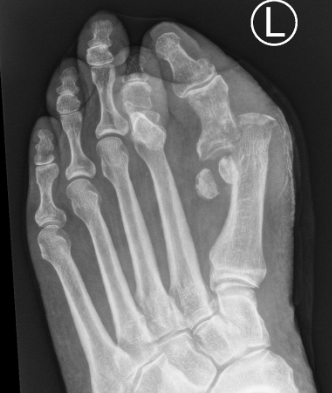

Interphalangeal joint dislocation

Pathology

Hyperdorsiflexion

P1 head dislocates plantar

Fractures

Xray

Blocks to closed reduction

Sesamoid interposition